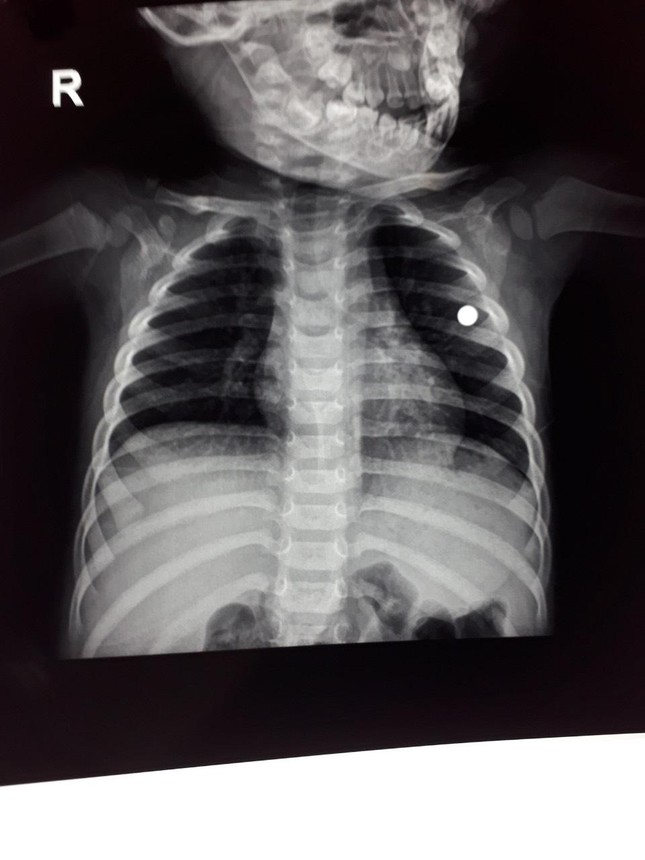

Ngày 20/2, thông tin từ Bệnh viện Nhi Thanh Hoá cho biết, các bác sĩ đã phẫu thuật thành công cho một cháu nhỏ bị viên đạn bi găm trong ngực trái do bị súng tự chế bắn. Bệnh nhân tên L.V.V (4 tuổi), ở xã Xuân Chinh, huyện Thường Xuân.

Theo thông tin từ gia đình bệnh nhân cho biết, ngày 18/2, trong quá trình chơi đùa, không may V. bị anh trai (5 tuổi) dùng súng cồn bắn vào ngực trái cạnh tim. Sau khi trúng đạn, cháu V. bị chảy máu nhiều, được đưa tới sơ cứu tại bệnh viện Đa khoa huyện Thường Xuân, rồi chuyển xuống bệnh viện Nhi Thanh Hóa cấp cứu. Các bác sĩ đã phẫu thuật lồng ngực trái gắp đạn ra. Tình trạng hiện tại bệnh nhân tỉnh táo, không còn nguy hiểm đến tính mạng.

Viên đạn trong ngực trái của cháu bé. Ảnh do Bệnh viện Nhi Thanh Hoá cung cấp

Ông Lương Văn Long - Chủ tịch UBND xã Xuân Chinh xác nhận sự việc xảy ra trên địa bàn. Bước đầu xác định bố cháu V. sử dụng súng cồn tự chế đi săn về quên tháo đạn. Khi để súng ở nhà, người anh nghịch súng không may bắn phải em. Hiện vụ việc đang được cơ quan chức năng xử lý.